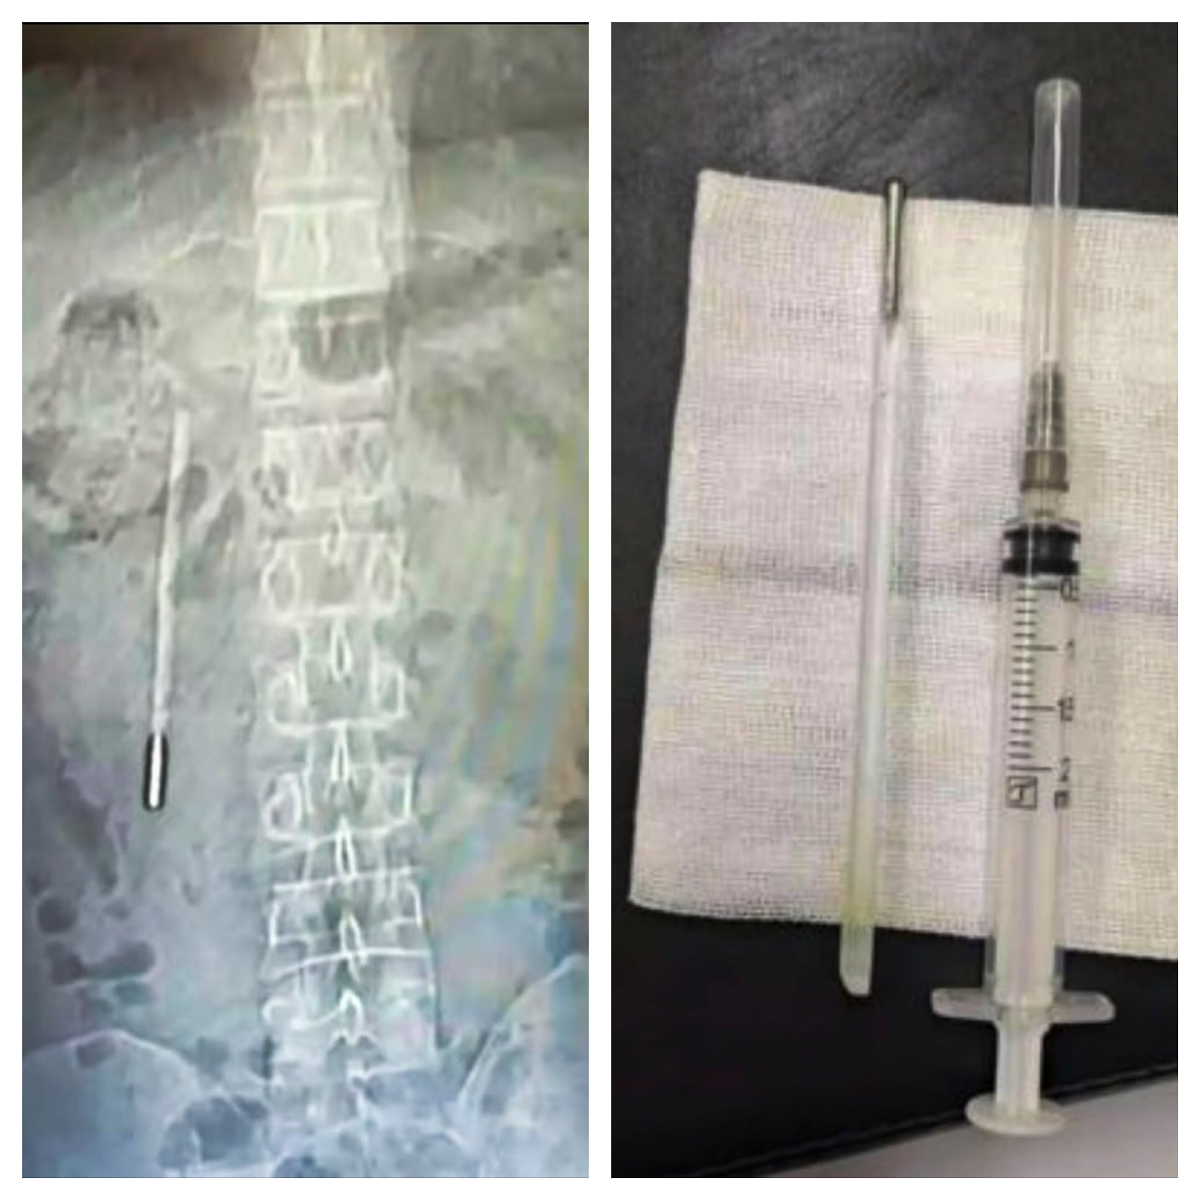

В Китае 32-летний мужчина по фамилии Ван обратился в больницу провинции Чжэцзян с жалобами на боли в животе. Обследование показало инородный предмет в двенадцатиперстной кишке. Позже выяснилось: это градусник, который пациент проглотил еще в детстве.

Медики удалили инородный предмет после обследования. Самое удивительное в этой истории – то, что градусник за два десятилетия остался цел. Стерлись только деления температуры, так что использовать его снова уже вряд ли получится. При этом врачи отмечали, что из-за положения термометра сохранялся риск серьезных осложнений, включая прободение кишки и внутреннее кровотечение.